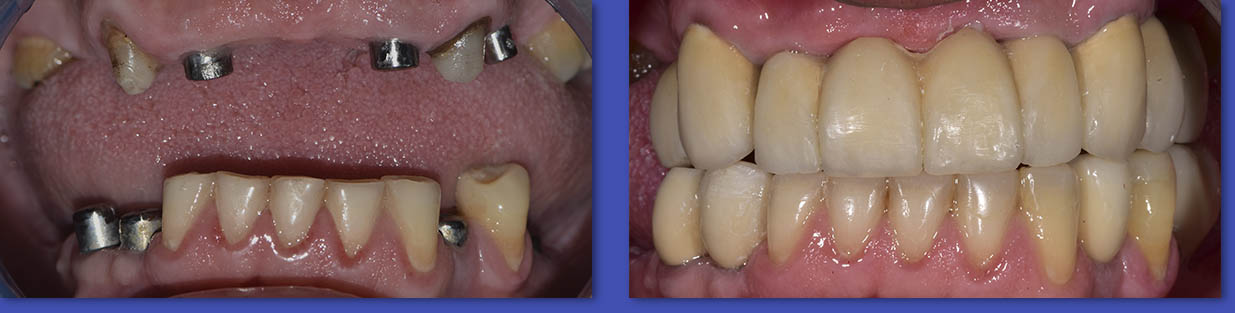

8. IMPLANTES DENTALES

Los Implantes de titanio vienen a ser hoy la mejor forma de recuperar los dientes perdidos. El porcentaje de éxito de los implantes esta cercano al 95%. Los Implantes son una prótesis que se inserta en los huesos maxilares y sobre ellas se pueden realizar rehabilitaciones tanto de uno como de varios dientes.

ANTES

DESPUÉS